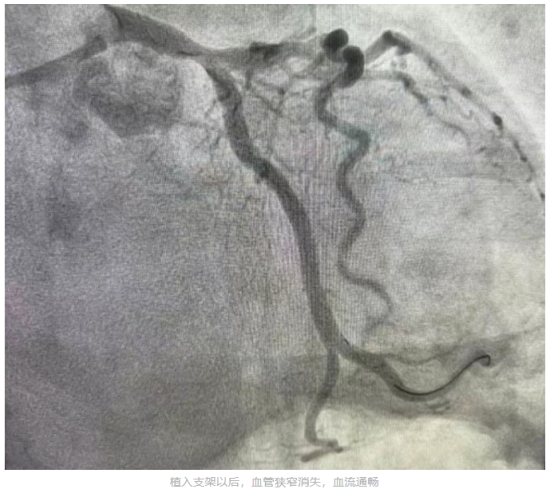

心血管内一科主任张国华到场后,结合患者心电图报告、临床症状及既往心脏病史,迅速诊断其为急性心肌梗死,并指导立即给予口服药物,建议其进行急诊冠脉造影检查及介入治疗开通血管。心血管内科介入团队迅速为李先生进行冠脉造影检查。检查结果显示,患者左冠状动脉回旋支完全闭塞,随时可能危及生命。经过血栓抽吸后血管开通,但病变处狭窄仍为95%。随后心血管内一科介入团队又为患者植入1枚支架。支架植入后患者病变狭窄完全消失,血流通畅,胸痛消失,意识状态恢复。